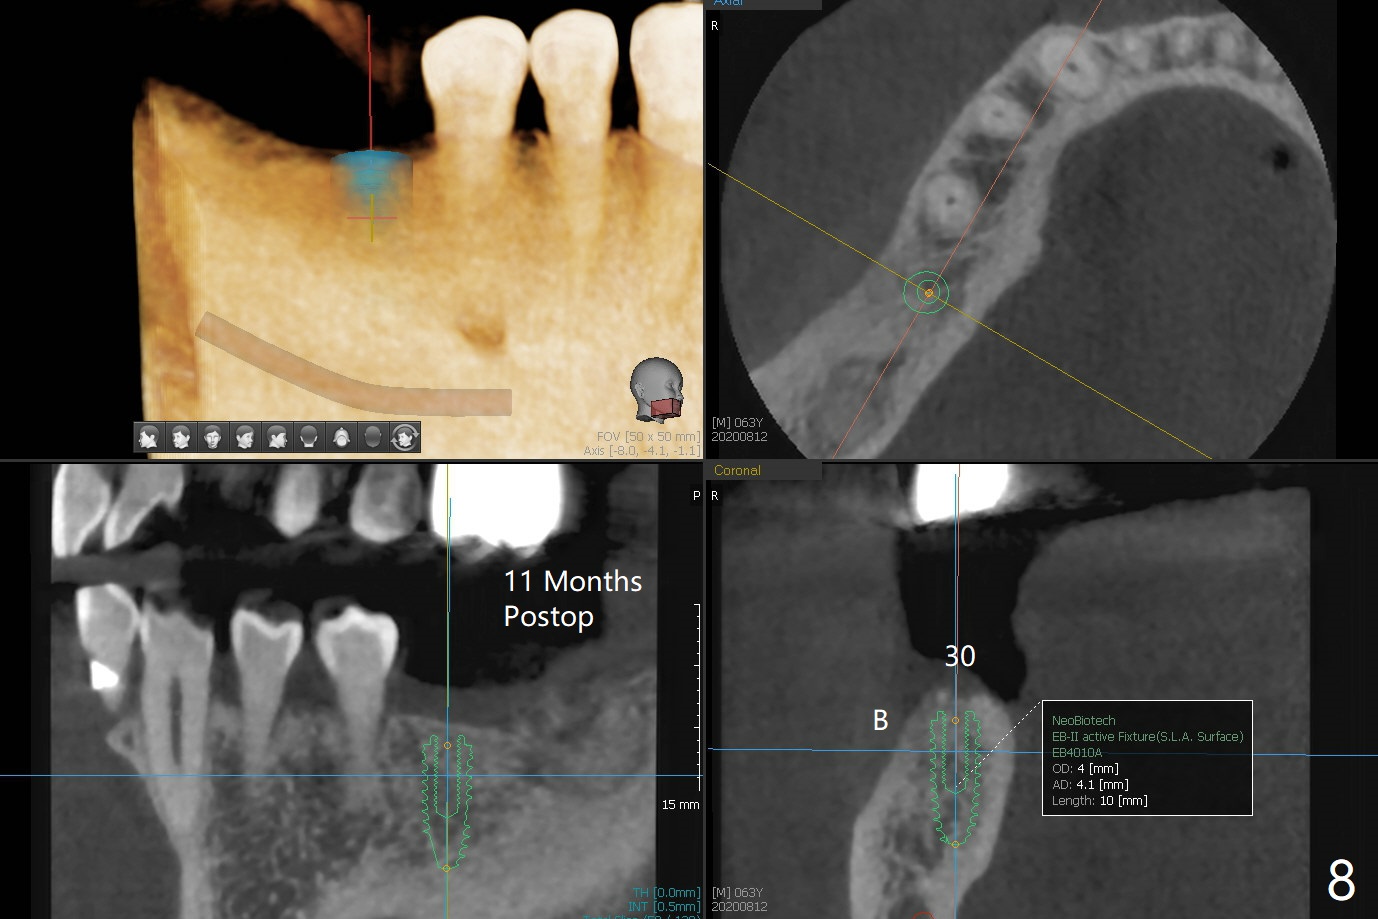

Since the tooth #31 is mesially shifted and tilted with mobility, it would not be a good distal anchor tooth for #30 implant placement with a surgical guide. It is extracted when an implant is placed at #3 so that autogenous bone harvested from the osteotomy at #3 will be mixed with allograft (Vanilla) and alloplast (Osteogen) for #31 socket preservation (Fig.3 M). After Osteogen plug and 6-month membrane are placed over the mixed graft, the socket is approximated with 5-0 PGA (Fig.1,2). The 6-month membrane appears to be retained 5 days postop (Fig.4). The socket reduces substantially nearly 1 month postop (Fig.5,6). The small 2nd molar socket (as compared to the 1st molar one) heals quick. PGA suture should be used more often (for more cases and repeat multiple times for secure closure). The bone density in the graft area increases 4 months postop (Fig.7). The graft remains in site nearly 11 months postop (Fig.8). The ridge #30 will be split with guide. In fact there is not much problem when the osteotomy moves lingual.